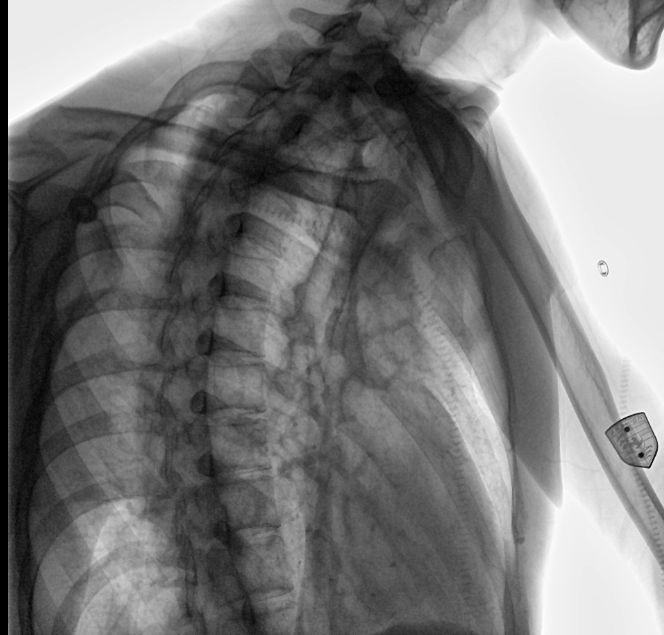

位于衡水市中醫(yī)醫(yī)院的動(dòng)態(tài)平板數(shù)字化X射線系統(tǒng)DTP571具備高速高清點(diǎn)片功能。這是一款對(duì)放射科十分友好的產(chǎn)品。因?yàn)樗迅咚俸透咔妩c(diǎn)片結(jié)合,既能方便影像技師有效地抓拍需要的病灶的影像,又能給予影像醫(yī)生清晰的影像進(jìn)行診斷。

動(dòng)態(tài)觀察診斷,實(shí)時(shí)高清點(diǎn)片